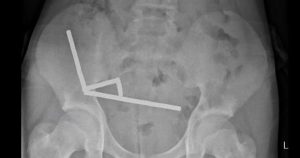

न्युझीलंडमध्ये 13 वर्षीय मुलगा पोटदुखीने त्रस्त होता, जेव्हा तो डॉक्टरकडे गेला, तेव्हा त्याला मागील काही दिवसांमध्ये काय काय खाल्ले असे विचारण्यात आले, यावर या मुलाने चकित करणारे उत्तर दिले. 100 हून अधिक छोटे-छोटे चुंबक गिळल्याचे त्याने सांगितले. डॉक्टरांनी मुलाच्या पोटाचा एक्सरे आणि अन्य तपासणी केली असता त्याच्या आतड्यात छोटे छोटे शेकडो चुंबक अडकल्याचे दिसून शॉपिंग साइट टेमूद्वारे खरेदी करण्यात आले होते.

चुंबक गिळल्यावर त्याच्या पोटात वेदना सुरू झाल्या. चार दिवसांनी पोटदुखी तीव्र झाली, तेव्हा तो डॉक्टरांकडे पोहोचला. त्याला देशातील नॉर्थ आयलँड येथील टौरंगा रुग्णालयात दाखल करण्यात आले. डॉक्टरांना तपासणीत मुलाने 100 अधिक उच्चशक्तीचे चुंबक गिळाल्याचे आढळून आले. जवळपास एक आठवड्यापूर्वी 80-100 छोटे नियोडिमियम चुंबक गिळल्याचे त्याने डॉक्टरांना सांगितले होते. परंतु नंतर डॉक्टरांना त्याच्या आतड्यांमध्ये जवळपास 200 चुंबक मिळाले आहेत.

चुंबकामुळे ईजा